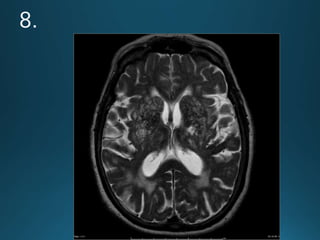

Cerebral Autosomal DominantArteriopathy with Subcortical Infarcts and

Leukoencephalopathy (CADASIL) is characterised by recurrent lacunar and

subcortical white matter ischaemic strokes and vascular dementia in young and

middle age patients without known vascular risk factors

autosomal dominant trait

recurrentTIA and dementia

MRI:

widespread confluent white matter hyperintensities . More circumscribed

hyperintense lesions are also seen in the basal ganglia, thalamus and pons

There is relative sparing of the occipital and orbitofrontal subcortical white matter 2,

subcortical U-fibers and cortex